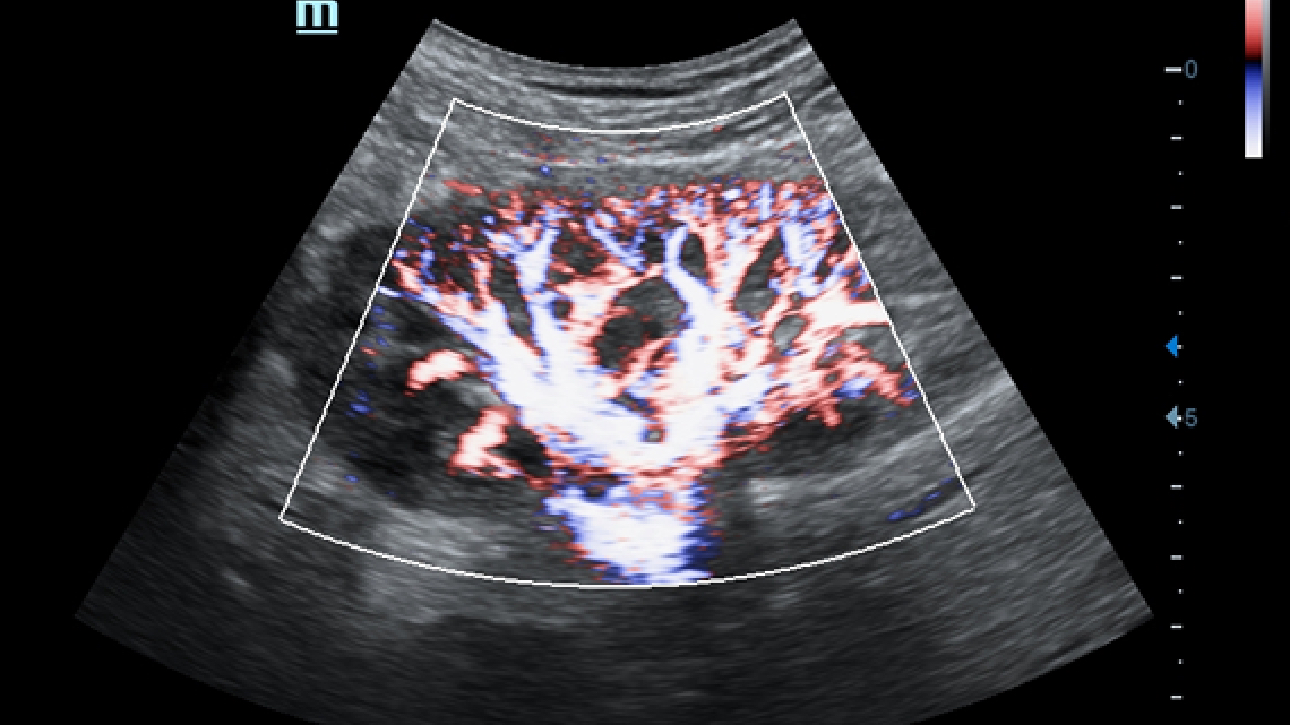

X-Insight ??? ??? ??? ??? ?? ??? ?? ?? ??????.

?????? ??? ???? ?? ???? ??? ??? ??? ???? ??? ??? ??? ?? ??? ???? ?????. ??? ?? ????? ???? ???? ??? ?? ??? ???? ?? ???? ??? ???? ???? ????.

???? ?? ??? ?????, X-Insight???? ??? DC-60 Exp ?? ??? ???? ???? ?? ??? ?? ??? ?? ???? ?????.

X-Insight??? ??? DC-60 Exp? ??? ??? ?? ?? ???? ???? ???(eXpress) ???, ???(eExceptional) ?????, ???? (eXceeding) ?? ??? ?? ????, ??? ???? ??? ??? ?? ???? ?????.